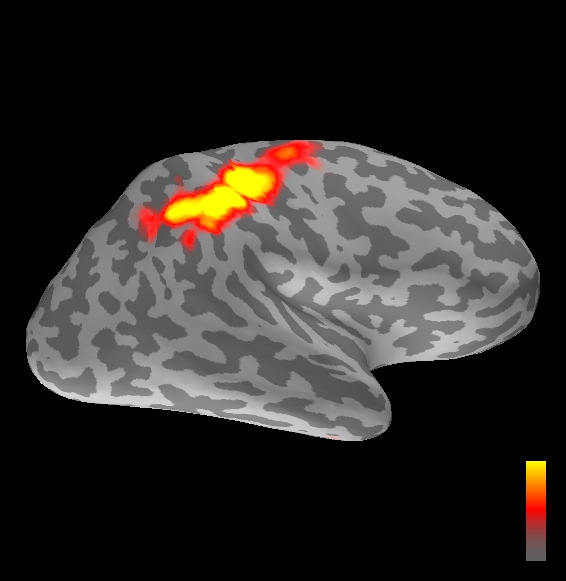

5.2 Results

We applied the ASMC sampler to MEG topographies taken from the above recordings by selecting specific time points according to the previous analysis; the parameter values in the algorithm were the same as those used for the analysis of synthetic data, with the only exception of the noise standard deviation , here estimated from the pre–stimulus interval. In order to validate the results of the ASMC, we also computed source estimates using three other methods: a PF, that approximates the posterior distribution for the current dipoles conditioned on the data up to the selected time point; dSPM, which is based on a distributed source model with an –prior, and consists in normalizing the Tikhonov regularized solution by the noise standard deviation; and sLORETA, which is similar to dSPM but is claimed to have a smaller localization bias. Figure 4 shows the results at , and ms after the stimulus onset. The results are visualized on a computer representation of the brain obtained by “inflating” the cortical surface: gray levels contain the anatomical information, light gray representing gyri and dark gray representing sulci; the activity estimate is coded in color scale, increasing from red to yellow. Importantly, this visualization allows activity in the sulci to be clearly visible; on the other hand, since neighbouring volumes may be moved apart by the inflation process, distinct activity regions are often due to underlying volumetric masses that are very close to each other.

Before describing the results, let us comment on the qualitative difference between the images produced by the ASMC sampler and the PF, on the one hand, and those produced by dSPM and sLORETA, on the other. First of all, we point out that all the quantities shown in the images of Fig. 4 are somehow related to the probability of activation at specific locations. Indeed, for both the ASMC and the PF we plot the approximation of the intensity measure (3.8); for any single grid point, this value can be interpreted as the probability of a dipole being at that location, while it integrates, over a given volume , to the mean number of dipoles within . As for dSPM, the represented quantity is a statistical value that is –distributed under the null–hypothesis of zero activity; as a direct consequence, it also yields a probability of activation, which is however not constrained to be dipolar. Similar considerations apply to sLORETA, although with a different statistical distribution. Importantly, the representation of the results is clearly affected by the setting of the visualization threshold. Owing to the explained differences between the methods, it seems reasonable to use a different value for each method. At the same time, since the plotted quantity is a probability of activation, it seems right to use the same thresholding for different time points. In this connection, the thresholds in Fig. 4 have been chosen by hand following the guidelines just outlined.

Using the same thresholding and parameters at different time points makes the four methods respond differently to the diverse intensities of the different sources. Whenever a stronger source is active, both sLORETA and dSPM will tend to produce widespread estimates, while weaker sources will be represented as small active areas. The behaviour of the ASMC and of the PF is the opposite: a stronger signal will lead to a precise localization of a dipolar source, and then to a focal marginal distribution for the location; a weaker signal will translate to higher uncertainty on the source position, and therefore a more widespread posterior map.

The phenomenon just described is indeed clearly visible in Figure 4. At ms, all the methods correctly identify the rather strong activation in the contra–lateral primary somatosensory cortex: the ASMC and the PF provide very focal maps, while dSPM and sLORETA provide compatible widespread estimates; dSPM also exhibits a more posterior peak which does not fit with the commonly agreed models of the response to median nerve stimulation; this may be due to the formerly described brain inflation.

At ms, the ASMC localizes two sources, one in the right hemisphere and a weaker one in the left hemisphere; these sources appear to be compatible, for timing and location, with the Posterior Parietal Contra and Parietal Opercular Ipsi described in Mauguiere et al. (1997). The PF finds the very same source in the right hemisphere, but it estimates no dipoles in the left one. Such discrepancy between these two methods, which are based on the same source model, is possibly due to two facts: first, thanks to its iterative nature, the ASMC is likely to explore the state space more thoroughly and is therefore more suited to identify weak sources; second, the log–uniform prior on the strength of the dipole moment in the ASMC has a wider range than the corresponding Gaussian prior in the PF. Slightly different results are provided here by dSPM and sLORETA. The activity estimate computed by dSPM seems very similar to that of ms, having the same spatial distribution with a weaker intensity. The estimate of sLORETA in the right hemisphere includes that of the ASMC and of the PF. Neither dSPM nor sLORETA find significant activity in the left hemisphere.

At ms, the ASMC localizes again two sources: a stronger one in the right primary somatosensory cortex, and a weaker one in the left posterior frontal area. Both of them seem to be compatible, for timing and location, with the results in Mauguiere et al. (1997), the left dipole corresponding to the Frontal Ipsi source. Once again, the other three methods only recover the stronger source.